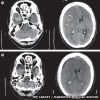

Questo è il quarto caso di ematoma cerebrale collegato all'headbanging (di cui uno ha portato alla morte del paziente), che può provocare seri danni al cervello facendolo "rimbalzare" contro il cranio.

Ma i rischi, spiegano i medici, rimangono minimi. "Non abbiamo niente contro l'headbanging" ha spiegato uno dei medici che ha curato il paziente, "e il rischio di danni cerebrali è molto molto basso. Certo se quest'uomo avesse assistito ad un concerto di musica classica l'incidente non sarebbe accaduto di sicuro. In generale però potete continuare tranquillamente a godervi la vostra musica metal".